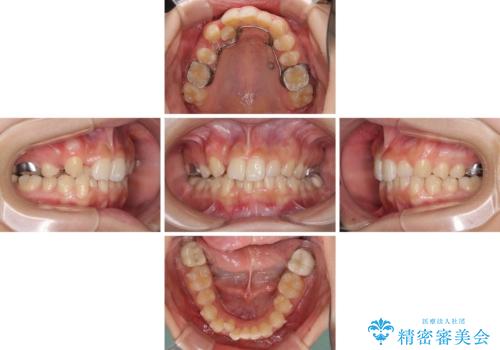

- 3年8ヶ月

- 治療費の目安: 95万円(税込)費用は治療当時の料金となります

インビザラインでは治療期間が延びることが予想されたため、ワイヤー矯正を提案しましたが、セラミッククラウンが多く、壊すあるいは傷が付く可能性があることから、長期間であってもインビザラインを選択されました。